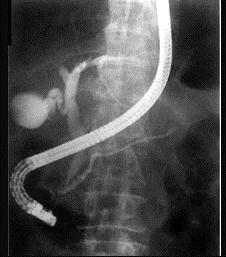

问题 下列各图为何种胆道造影方式 ( )

选项 A、内镜逆行胰胆管造影(ERCP) B、磁共振胆胰管造影(MRCP) C、静脉胆道造影 D、经皮肝穿刺胆道造影(PTC) E、口服胆囊造影

答案 A